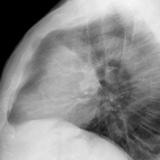

Thymic carcinoma Lat

Date: 08/15/2012

Views: 10195